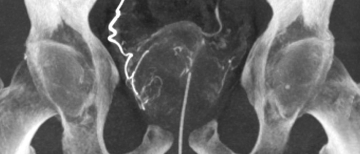

Radiological Sciences About Us Message from the Chair Outreach Contact Us Education & Training Residency Programs Diagnostic Radiology Residency Integrated Interventional Radiology Residency Independent Interventional Radiology Residency Fellowship Programs Resident & Fellow Resources Research Faculty Labs & Research Centers Divisions Abdominal Imaging Breast Imaging Cardiothoracic Imaging Musculoskeletal Imaging Neuroradiology Imaging Nuclear Medicine and Molecular Imaging Pediatric Imaging Vascular & Interventional Radiology Clinical Expertise Clinical Programs Faculty Prostatic Artery Embolization Home About Campus & Community Resources Communications & Public Relations Office Radiological Sciences: Clinical Expertise > Clinical Programs > Prostatic Artery Embolization Interventional Radiology Approaches to Benign Prostatic Hyperplasia Prostatic Artery Embolization (PAE) is a minimally invasive treatment designed to alleviate lower urinary tract symptoms caused by benign prostatic hyperplasia (BPH). BPH refers to the noncancerous enlargement of the prostate gland, affecting approximately one in four men by age 55 and half of men by age 75. As the prostate enlarges, it may partially obstruct the urethra, leading to bothersome urinary symptoms. These symptoms include: urinary incontinence increased frequency and nighttime urination urinary urgency pain during urination For men who are not satisfied by their medical therapy and are either ineligible for traditional surgery or prefer a less invasive approach, PAE is an effective solution. Via a small puncture in the upper thigh or arm, an interventional radiologist (IR) guides a catheter to the vessels supplying blood to the prostate. By blocking these blood vessels using tiny particles, PAE reduces the size of the prostate gland, providing relief from urinary symptoms without the need for major surgery. Patient Care Please visit our healthcare website for more information on PAE and to determine if you qualify for this procedure. PAE SERVICES